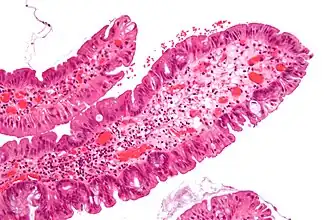

Tubular adenoma 2% at 1.5 cm[12] Low to high grade dysplasia[13] Over 75% of volume has tubular appearance.[14]

Tubulovillous adenoma 20% to 25%[15] 25–75% villous[14]

Villous adenoma 15%[16] to 40%[15] Over 75% villous[14]